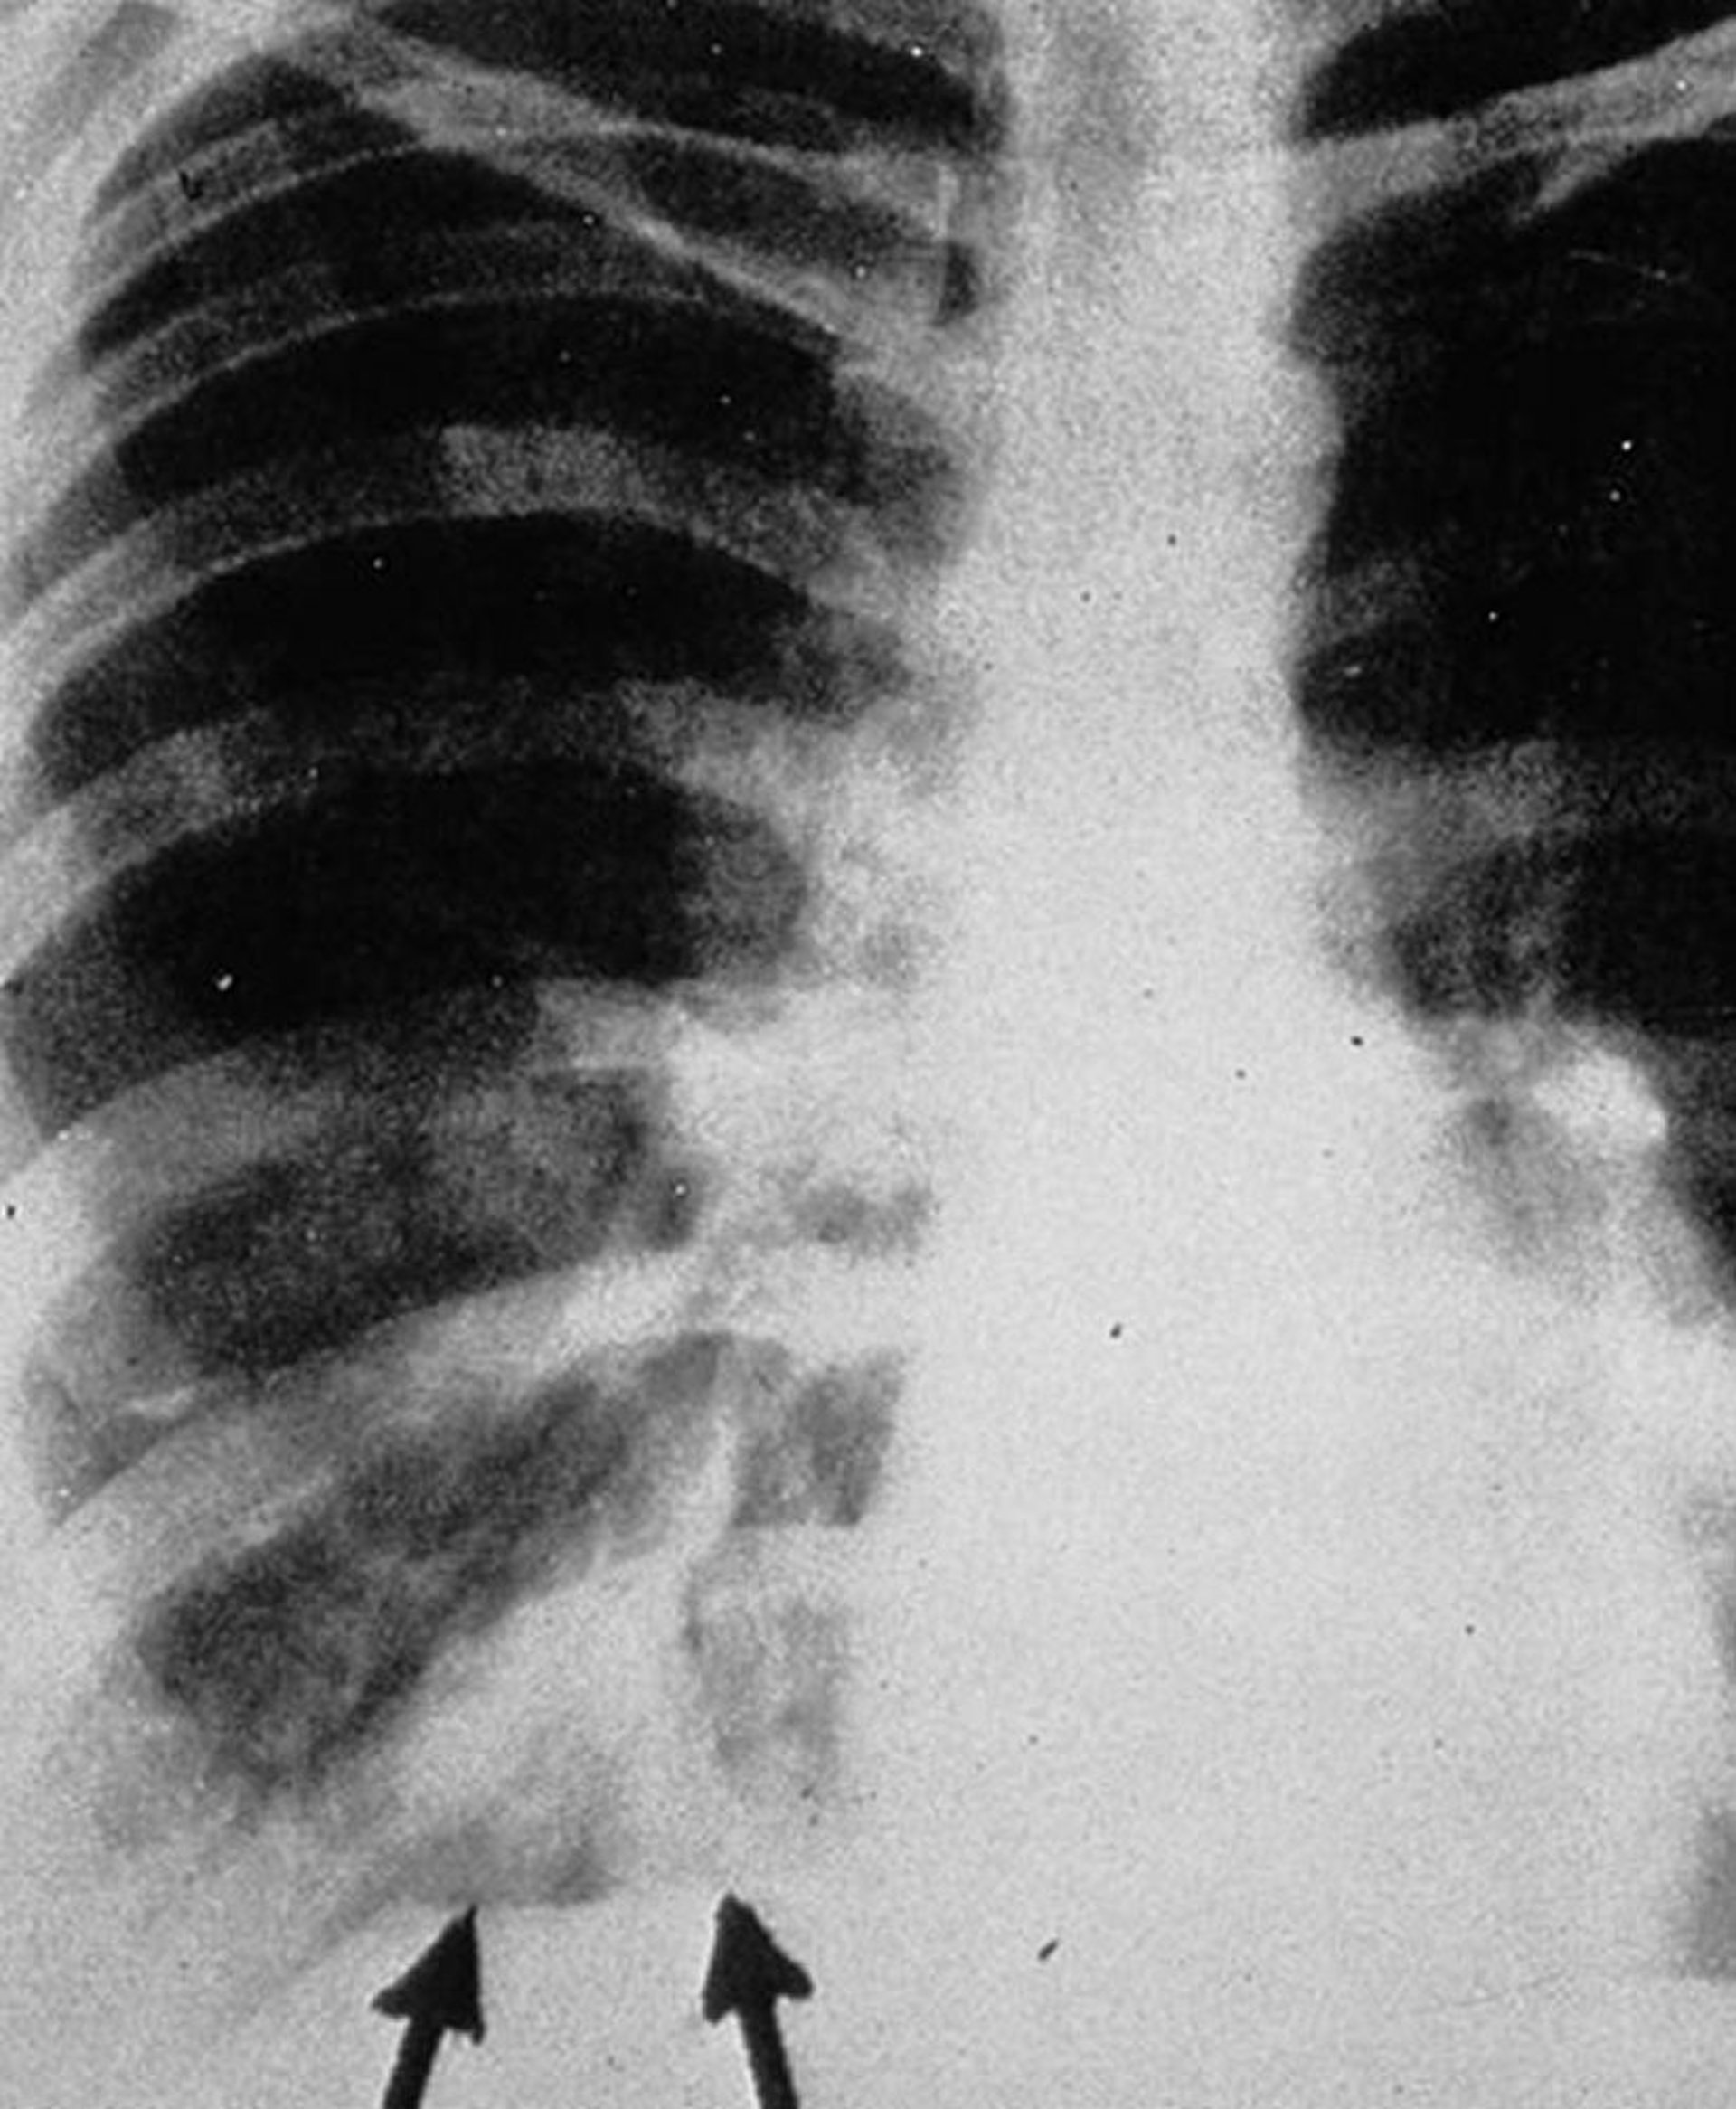

La radiografia del torace antero-posteriore mostra ombre a "dito guantato" (frecce), che appaiono come densità tubulari ramificate che rappresentano essudati intrabronchiali con ispessimento della parete bronchiale.

By permission of the publisher. Da Groll A, Walsh T. In Atlas of Infectious Diseases: Fungal Infections. Edited by GL Mandell and RD Diamond. Philadelphia, Current Medicine, 2000.